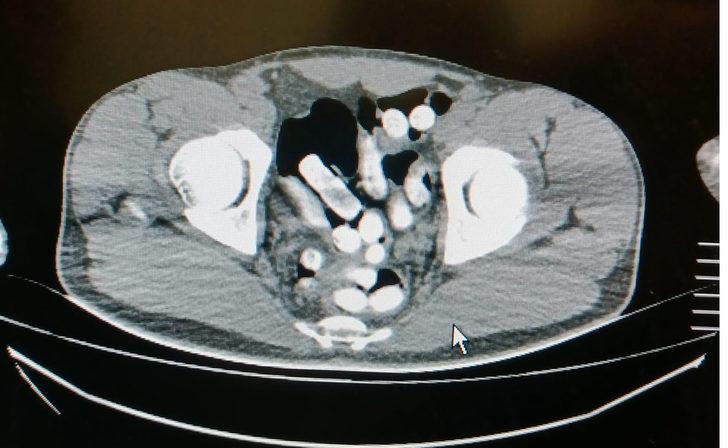

Gözaltına alınarak Ağrı Eğitim ve Araştırma Hastanesi'ne götürülen şüphelinin çekilen röntgeninde mide ve bağırsaklarında uyuşturucu olan kapsüller bulunduğu belirlendi. Mehran N'nin mide ve bağırsaklarında, 102 kapsül halinde 1 kilo 126 gram Afyon sakızı bulundu.